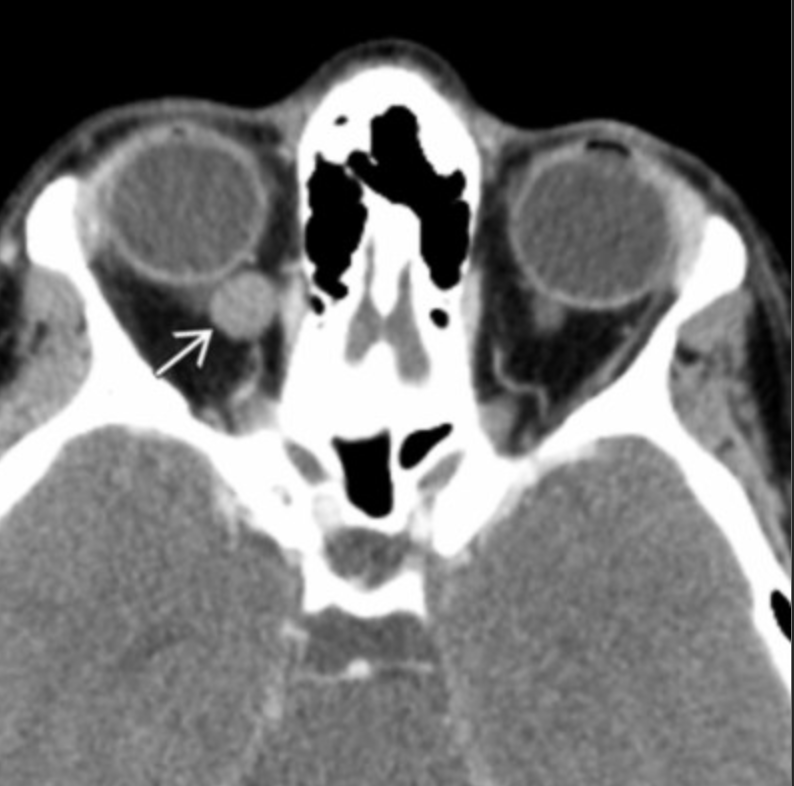

Angiolymphatic malformation

• Multiloculated cystic and solid mass

• Possible adjacent osseous remodeling secondary to persistent compression on bone

• Fluid-fluid levels (Rb does not have)

• Less commonly have calcs (Rb has calcs)

• Extra and intraconal

• Proptosis and swelling (Rb may have some of this but leukocoria and vision loss is key)